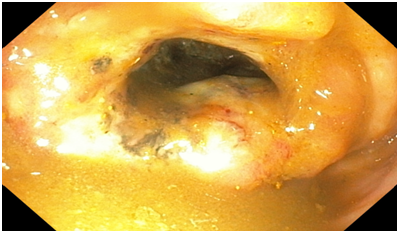

Figure 4 An endoscopic image of the Descending colon showing normal appearance.